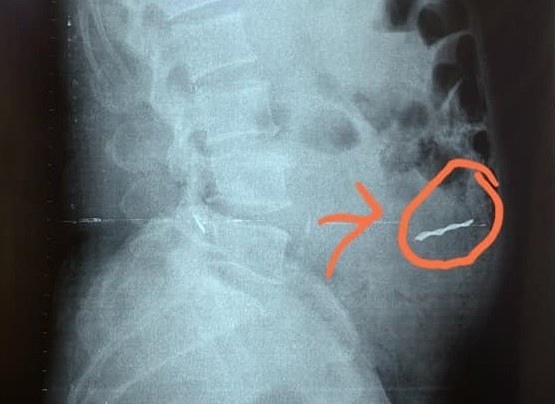

Các bác sĩ Bệnh viện Nhi đồng Thành phố (TP.HCM) vừa nội soi gắp viên sỏi có kích thước 15x15 mm cho bé trai T.P.V. (3 tuổi, ngụ quận 8, TP.HCM).

be trai nuot vien soi thuy tinh trong ho ca anh 1

Viên sỏi thủy tinh biết Q đã nuốt vào bụng.